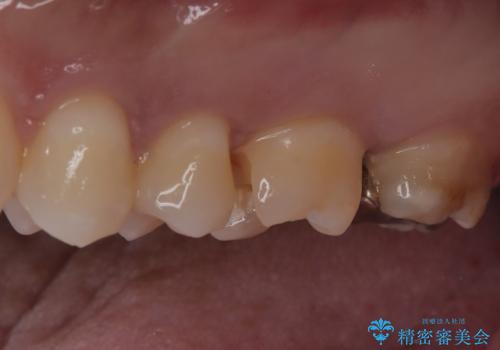

- 定期健診にて虫歯を見つけたためセラミックインレーにて修復しました。

綺麗に仕上がり患者さんも非常に満足されていました。

当院でのセラミックインレーはラバーダム防湿をして接着しております。